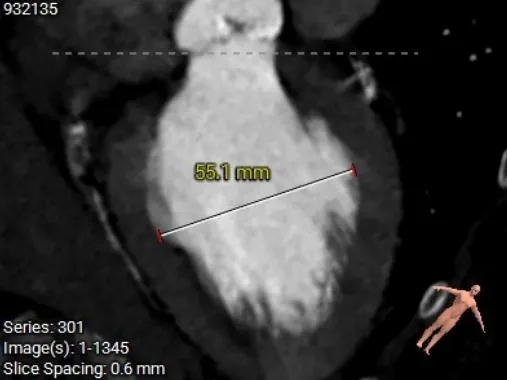

CASE Ⅲ

重度钙化伴低EF的一站式PCI+TAVR

心脏超声

超声测量:主动脉瓣呈三叶启闭,瓣叶呈结节样增厚,回声增强,开放受限。收缩期二、三尖瓣可见少量反流。收缩期主动脉瓣上可见高速血流,最高流速约505cm/s,估测平均跨瓣压差约71mmHg。EF=38.9%

诊断意见:

主动脉瓣病变-重度狭窄,轻度关闭不全

二尖瓣后叶瓣环钙化,轻度关闭不全

三尖瓣轻度关闭不全

术前CT分析

主动脉根部测量

Annulus 20.7mm

LVOT 21.3mm

钙化积分 612

SOV

27.9*26.8*27.1mm

STJ 22.6mm

AAO 28.8mm

左室测量

左室内径可,心室壁增厚,心尖较薄,注意导丝位置及形态,避免左室损伤。